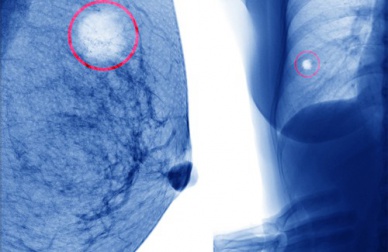

Les mammographies n’endommagent pas les seins. Des coups accidentaux ne provoquent pas le cancer du sein. La ponction (l’injection d’une aiguille permettant d’aspirer le contenu des kystes) ne répand pas le kyste dans le sein.